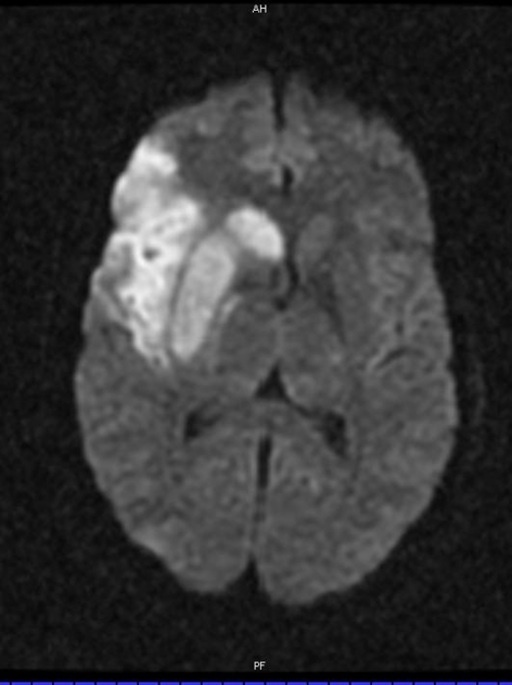

Image on left is SWI

Image on right is DWI

Stroke Syndrome:

In a right-handed patient:

Right superior division MCA